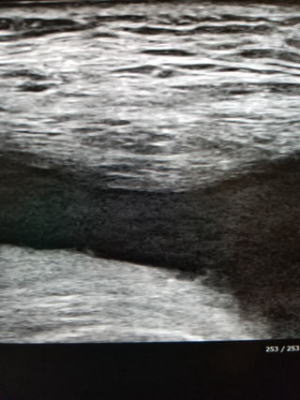

ご本人よりなんかすっきりしてきました。腫れも触れませんとのこと。レントゲンで石灰化は消失しています。また超音波でもかなり縮小してきています。触診で硬結は触れませんでした。

写真:アキレス腱断裂 超音波画像 最大底屈して断裂部(GAP)が十分寄るかどうかチェックしています。